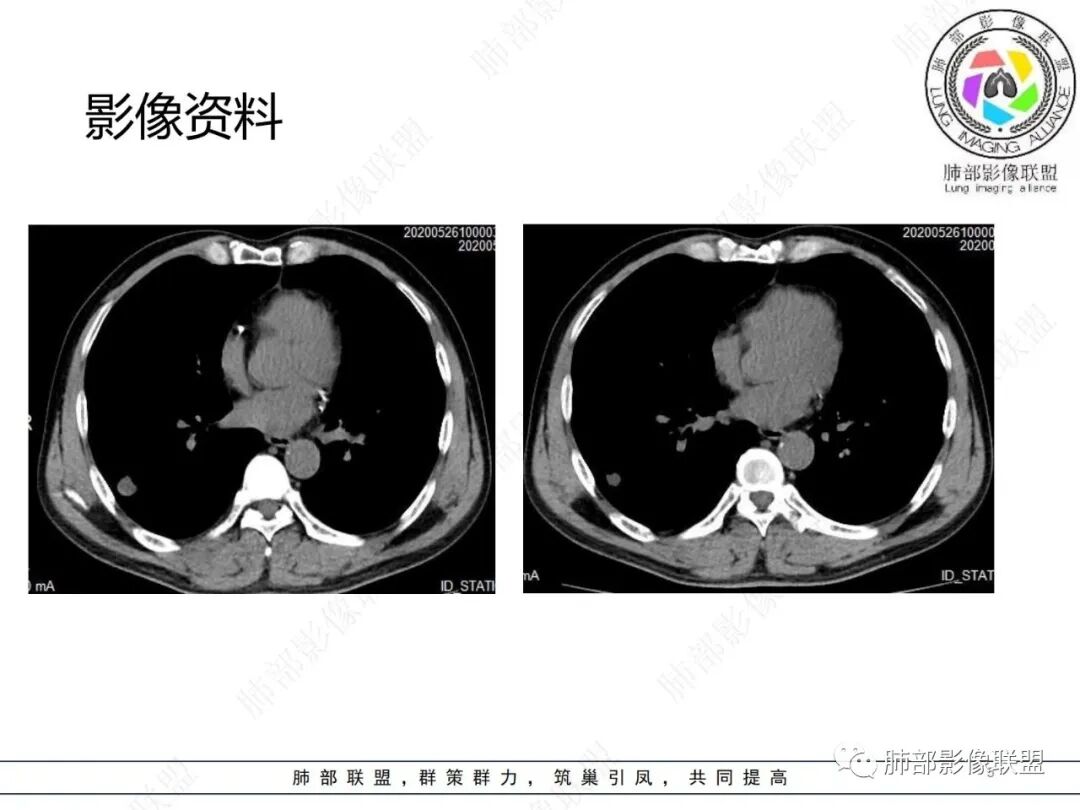

此病例中结节,与支气管无关系,边缘清晰,形态规则,缺乏张力,未见典型的分叶及毛刺,病灶周围磨玻璃为部分容积效应所致,肺门纵隔未见肿大淋巴结,良性病变可能性较大,肺部的良性肿瘤中,最常见的是错构瘤,其次是硬化性肺细胞瘤(PSP),第三是孤立性纤维性肿瘤(SFT)。

恶性病灶容易想到孤立转移灶或大细胞肺癌等,病史以及强化特点等不大支持。

硬化性肺细胞瘤

大多无分叶,血供丰富,通常增强幅度高于肺腺癌(本例强化不符合);部分有钙化,大多有血管支气管贴边征,血管离开时比原来细一些,即“留下买路钱”(本例强化不符合),约30%的病例周边有淡薄的出血晕,磨玻璃密度,边界模糊(本例强化不符合)。

综上所述,错构瘤可能性最大